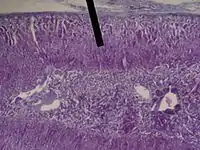

The zona fasciculata (sometimes, fascicular or fasciculate zone) constitutes the middle and also the widest zone of the adrenal cortex, sitting directly beneath the zona glomerulosa. Constituent cells are organized into bundles or "fascicles".

The zona fasciculata chiefly produces glucocorticoids (mainly cortisol in humans), which regulate the metabolism of glucose. Glucocorticoid production is stimulated by adrenocorticotropic hormone (ACTH), which is released from the anterior pituitary, especially in times of stress as part of the fight-or-flight response. The zona fasciculata also generates a small amount of weak androgens (e.g., dehydroepiandrosterone). The main source of androgens will come from the zona reticularis region. In certain animals such as rodents, the lack of 17alpha-hydroxylase results in the synthesis of corticosterone instead of cortisol.